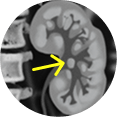

A 74-year-old male with CKD presented with hydronephrosis of the left kidney and underwent stent placement.

Ureteroscopy and biopsy confirmed a large papillary renal pelvis tumor consistent with LG-UTUC.